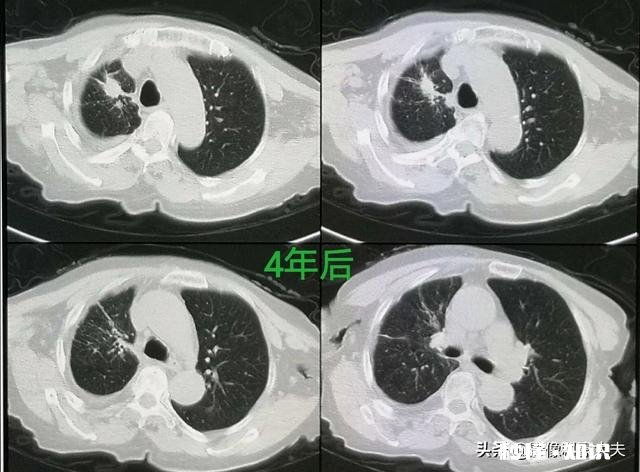

文章插图

这是一位甲状腺癌多发肺转移的病人,通过化疗为主的综合治疗,已经生存4年半了 。

真是一位81岁的老夫人 , 肺腺癌晚期侵犯胸膜,引起大量胸腔积液 。通过靶向治疗已经生存4年多,今年85岁了 。